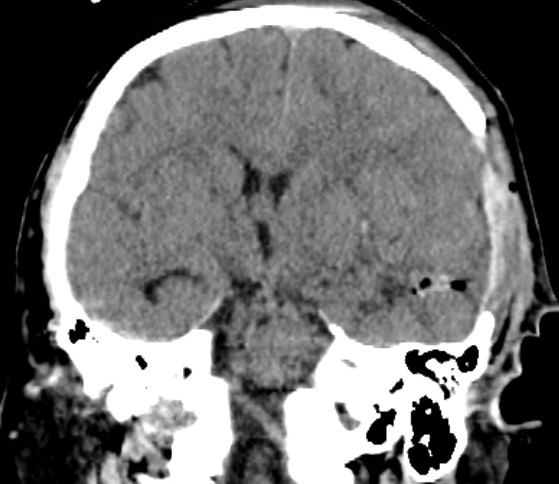

急诊头部CT显示左颞顶巨大脑内血肿,中线结构移位,脑疝

术后4小时CT复查术区干净,AVM已切除,动脉瘤夹闭良好